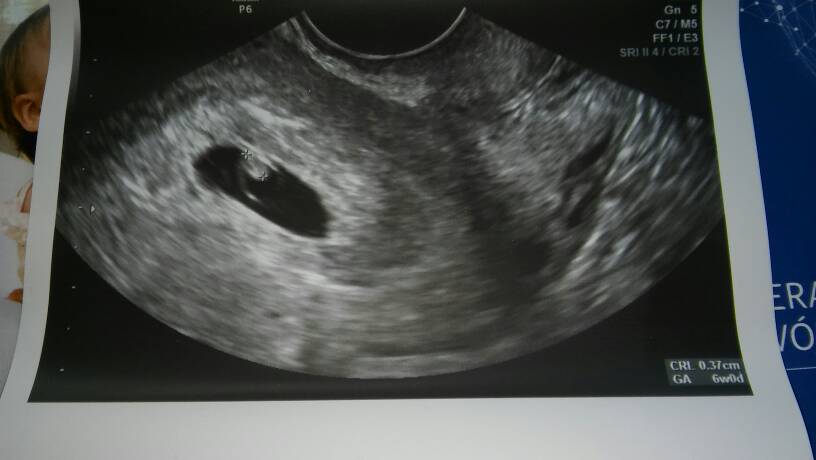

Dziękuję, u mnie jest trochę zbyt pięknie. Pierwszy cykl i od razu zapłodnienie. Nie plamię tfu, tfu, dobrze się czuję. Za bardzo mi zależy. Ktoś słyszał serduszko w 6 tygodniu?

Kurde to u mnie pewnie też serduszka nie będzie. Kiedy wg gina miałaś owu?